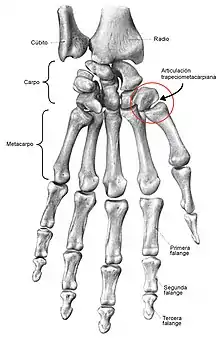

- Articulaciones en silla de montar, selar o de encaje recíproco: reciben su nombre porque su forma es similar a la de una silla de montar. Por ejemplo, la que está entre el primer metacarpiano y el hueso trapecio (articulación trapeciometarcarpiana) y la articulación esternoclavicular.

- Articulaciones condiloideas o elipsoidales: se forma donde dos huesos se encuentran unidos de forma irregular y un hueso es cóncavo y otro convexo. Ejemplos son la articulación temporomaxilar, occipitoatloidea, metacarpo falángicas y metatarsofalángicas.